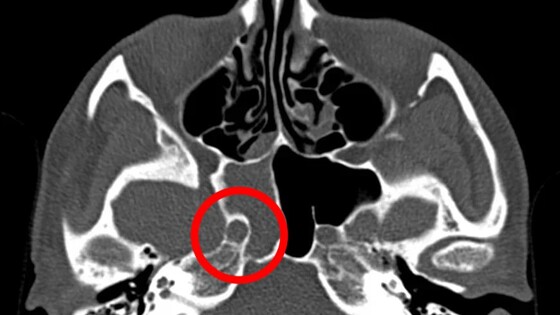

В Нижнем Новгороде врачи удалили грибок из пазухи носа пациентки, страдавшей от сильных головных болей. Об этом сообщает главред ИА «Стационар-Пресс» Алексей Никонов. Жительница Нижнего Новгорода, долгое время связывавшая свои мучительные головные боли с магнитными бурями, обратилась к врачам и оказалась на операционном столе. Настоящей причиной недомогания оказался грибок, разросшийся в основной пазухе носа. На видеоэндоскопических снимках, сделанных во время операции, отчетливо виден тёмно-коричневый грибок, глубоко расположенный в пазухе. Диагноз был поставлен после компьютерной томографии, которая выявила патологические изменения в области околоносовых пазух. По словам ЛОР-хирурга Григория Белозерова, операция проходила в зоне повышенного риска — буквально в миллиметре от внутренней сонной артерии, питающей головной мозг. Малейшая ошибка могла привести к необратимым последствиям. Ранее на сайте pravda-nn.ru сообщалось о том, что футзалиста «Торпедо» Антона Оппера прооперировали в Нижнем Новгороде.